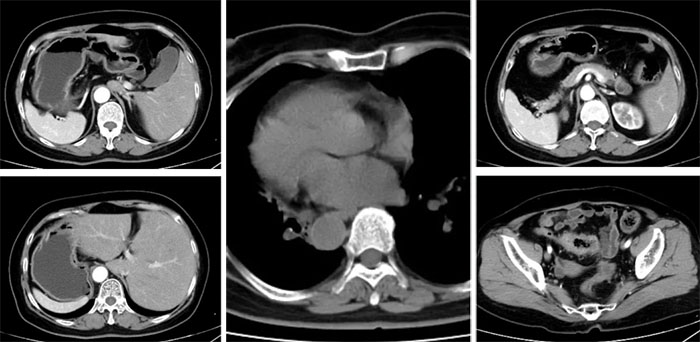

日前,我院成功救治了一位极为罕见的“镜面人”患者。如同镜子中所呈现图像与实际方向相反一样,“镜面人”的五脏六腑也与常人的位置完全相反,这就是罕见的内脏反位。一般来说,“镜面人”的发生概率大约在百万分之一左右。

三个多月前,谢阿姨发现自己时常出现腹痛腹胀等不适感,而且出现排便规律改变,但是那时候谢阿姨未在意。直到最近发现大便中带血,这才引起警惕。在我市其他医院做肠镜检查后发现,谢阿姨不幸患上了乙状结肠占位性病变,病理显示为腺癌。紧张不已的谢阿姨四处寻医,在亲朋好友介绍下得知我院已经成熟开展并成功完成了上千例腹腔镜下结直肠癌手术。最终在家人的陪同下,谢阿姨来到我院普外一科进行诊治。幸运的是,谢阿姨在我院完善检查后,并未发现有远处转移,可以行手术治疗。但是,影像检查同时也发现谢阿姨是位完全内脏反位的“镜面人”。